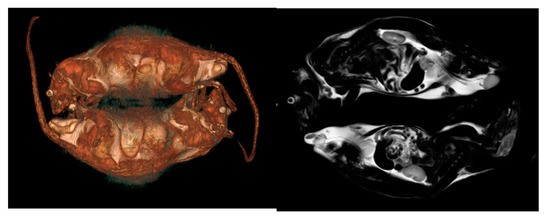

3.1. Computed Tomography (CT)

3.2. Magnetic Resonance Imaging (MRI)